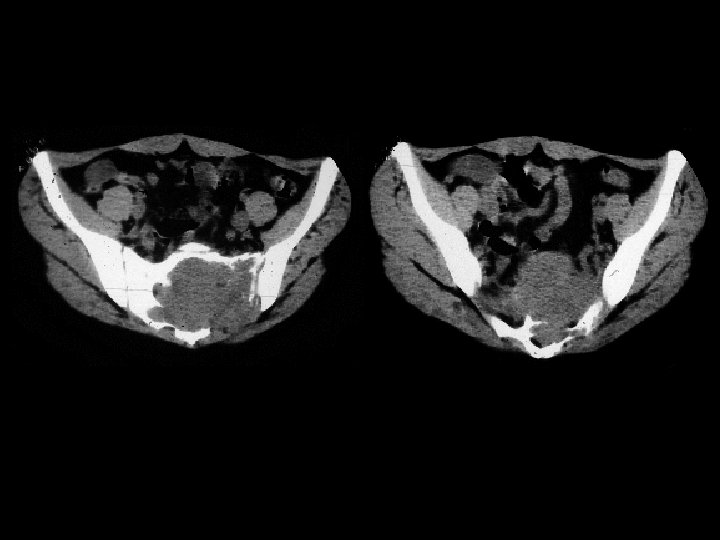

Neuroblastoma • Findings: – Bone scan shows increased uptake in the mid abdomen of a child – MR scan shows a corresponding soft tissue mass with scattered T 1 low sign foci = Ca 2+ • ddx: – NONE! – This is an Aunt Minnie!